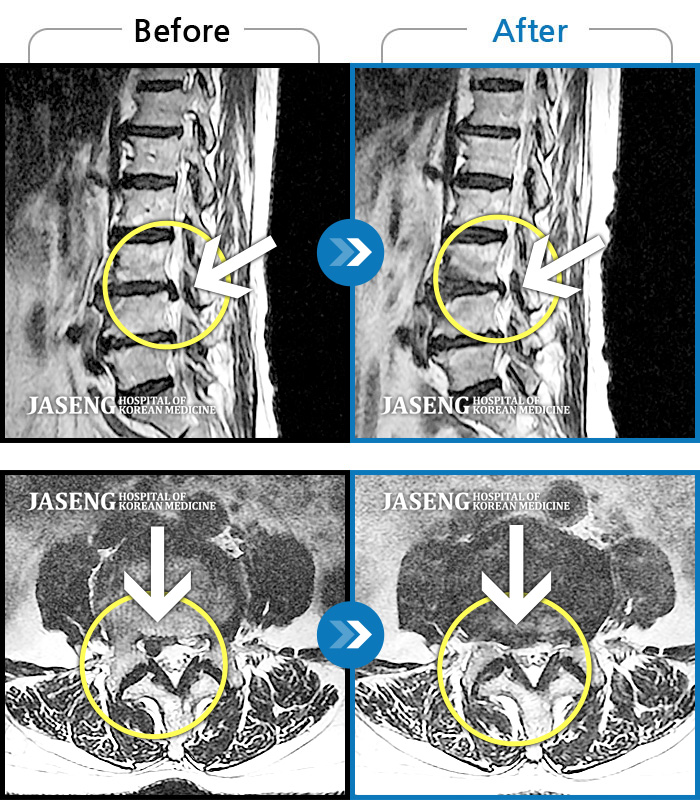

허리, 좌측 골반부터 좌측 다리로 통증 및 저림이 지속되고 좌측 다리의 감각이 둔함

촬영시기

2024.09.30 ~ 2025.11.25

2025.12.05